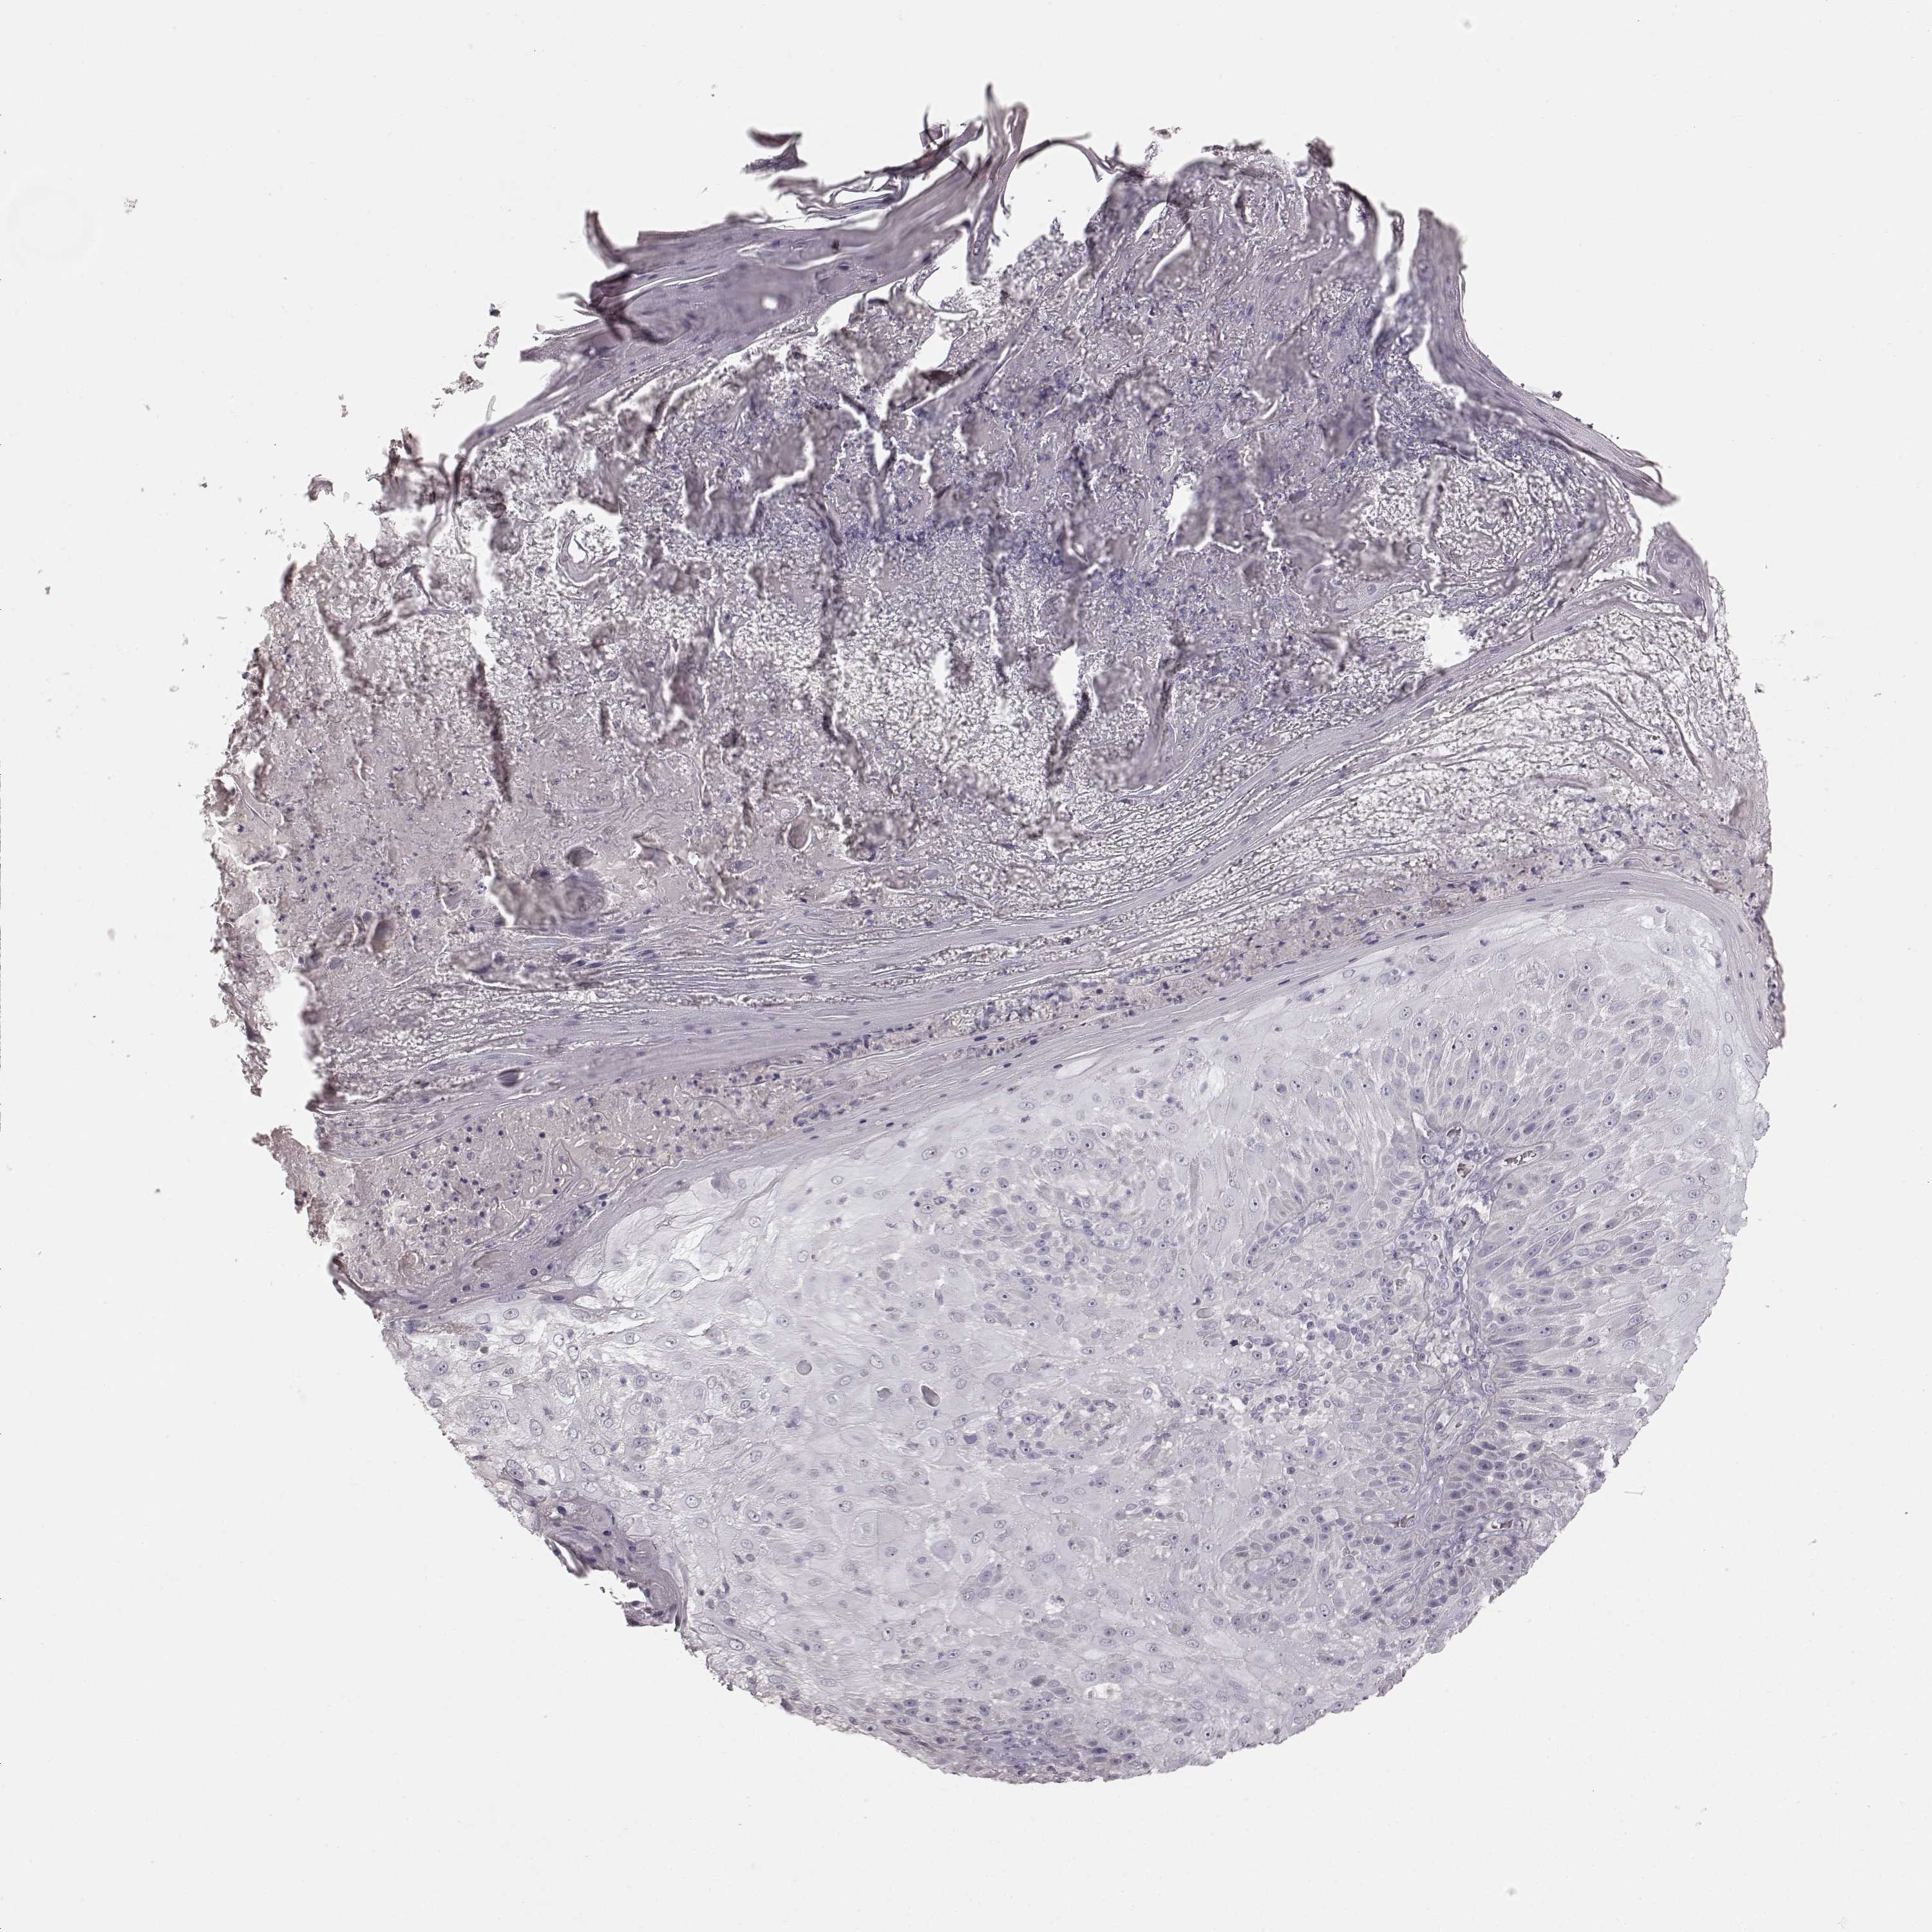

Basal cell and squamous cell cancer

SKIN CANCER - Protein expressioni

A mouse-over function shows sample information and annotation data. Click on an image to view it in a full screen mode. Samples can be filtered based on level of antibody staining by selecting one or several of the following categories: high, medium, low and not detected. The assay and annotation is described here.

Antibody stainingi

Antibody staining in the annotated cell types in the current human tissue is reported as not detected, low, medium, or high, based on conventional immunohistochemistry profiling in selected tissues. This score is based on the combination of the staining intensity and fraction of stained cells.

Each image is clickable and will lead to virtual microscopy that enables deeper exploration of all samples and also displays staining intensity scores, fraction scores and subcellular localization as well as patient and tissue information for each sample.

Antibody HPA039361

Basal cell carcinoma

Squamous cell carcinoma, NOS